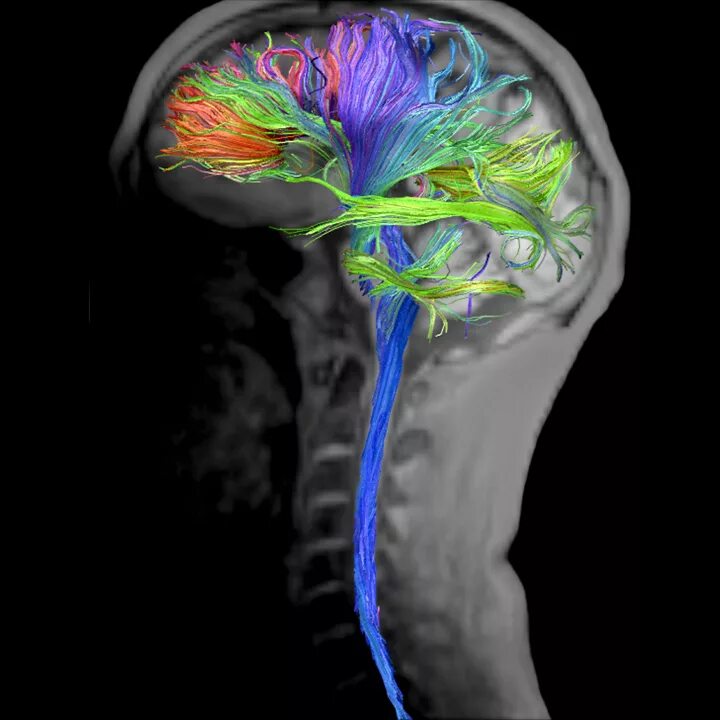

Мрт диффузия всего тела